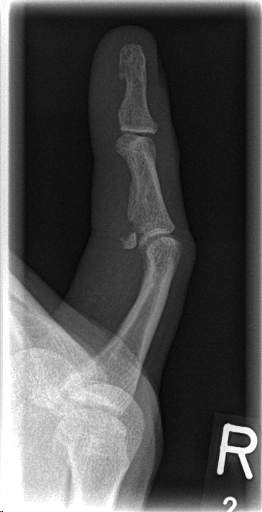

... dann gibt es noch Mittelblocker mit "Übereifer" beim Training! Und nicht zuletzt gefährdete Zuspielwunder ...